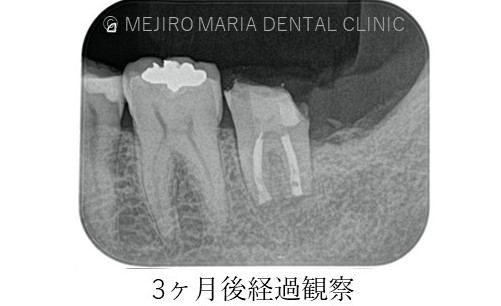

違和感や痛みは術後1ヶ月程で消失し、3ヶ月後には術直後に見られていた左下7番根尖部に確認できた透過像も消失し、順調に骨が作られていることが確認できます。

今後、最終補綴に移行し、1年後の経過観察を行う予定です。